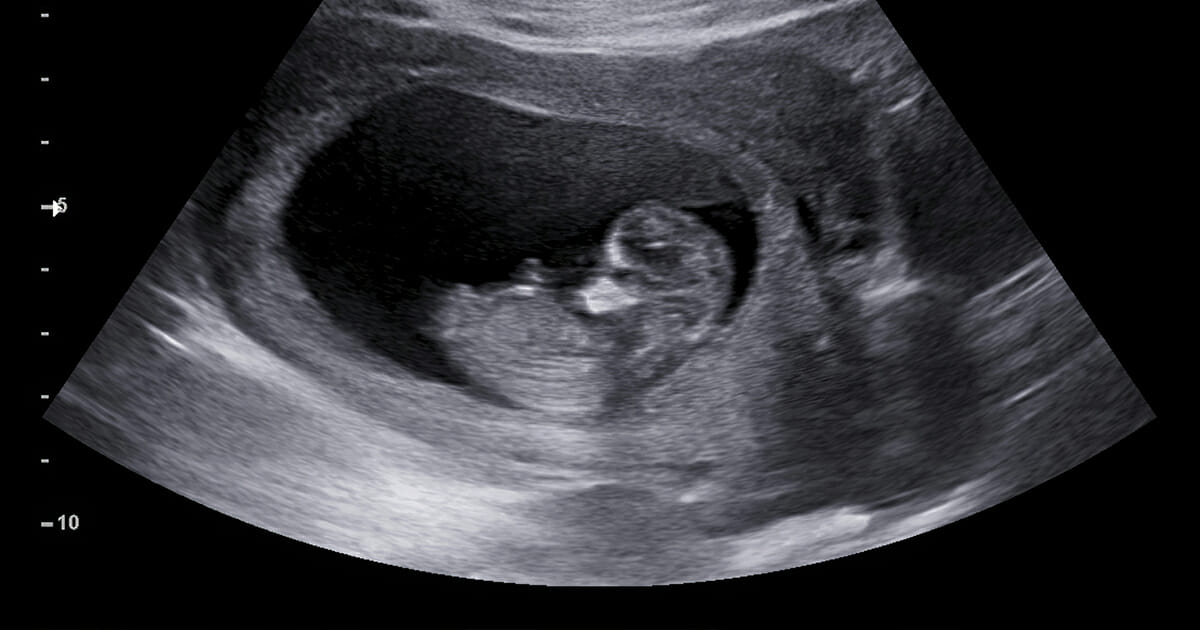

Halva tiden av graviditeten hade passerat smärtfritt när 28-åriga Rachel Bailey plötsligt fick en stor blödning. Med oro för barnet åkte Rachel in till sjukhuset för att få läkarna att titta så att barnet var okej, vilket det var. Däremot visade röntgen något som inte skulle vara i kroppen nära hennes barn, vilket The Epoch Times rapporterat om.

En massa på en längd av sex centimeter syntes i Rachels kropp, och efter att ha genomgått en MRI och biopsi kunde läkarna konstatera att Rachel hade fått en cancertumör som var stor som en vindruva i njurarna.